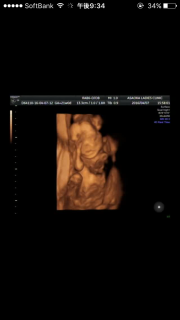

写真:21w0d:cnさん

照れ屋さんなのか初めはお顔を両手で隠していたんですが、先生が画面を見ながらゆっくり説明してくれてる間に油断したのかな?しっかりこっちを向いてかわいいお顔を見せてくれました♪たぶん女の子、だそうです!すでに愛おしくてたまりません(*^^*)